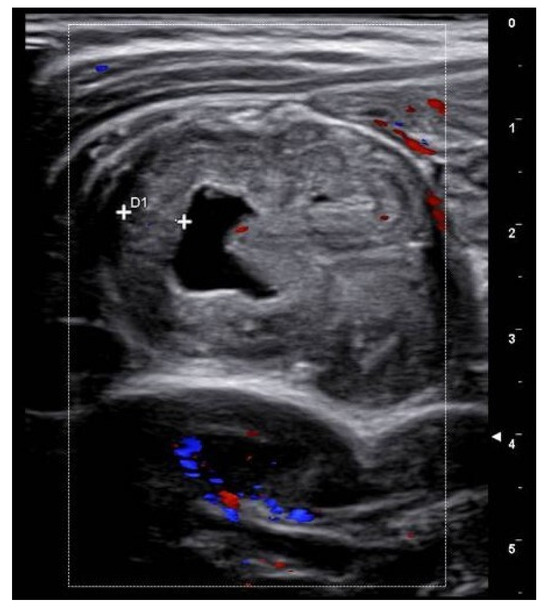

Figure 5.

Case 3—Endoscopic image showing fecal residues with melena appearence.